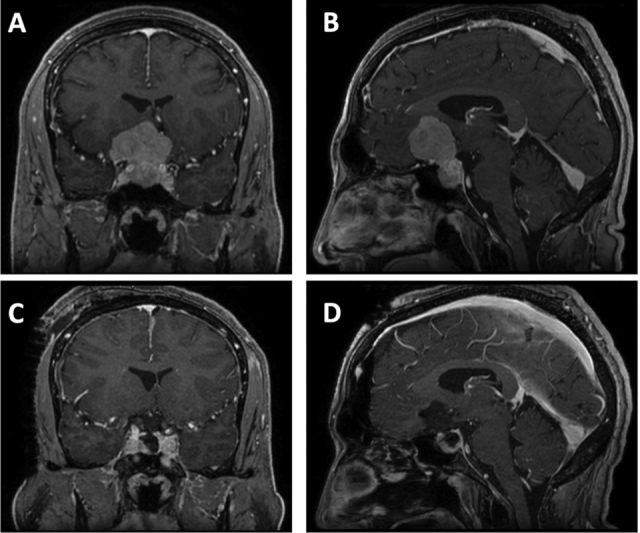

Collision tumors involving the sella are rare. Intrasellar collision tumors are most commonly composed of a combination of pituitary adenomas and pituitary neuroendocrine tumors; however, collision tumors consisting of a pituitary adenoma and intrasellar meningioma are exceedingly rare. The authors present the case of a 47-year-old man who presented with progressive right eye vision loss. Magnetic resonance imaging showed a large, heterogeneously enhancing sellar mass with suprasellar extension. Using a transcranial approach with a right subfrontal craniotomy, near-total resection of the mass was achieved. Histologic analysis confirmed a diagnosis of a gonadotroph adenoma with concomitant clear cell meningioma (CCM). This patient was discharged with improvement in visual acuity and no signs of diabetes insipidus. Given the indistinguishable radiographic characteristics of pituitary adenoma and CCM, a preoperative diagnosis of a collision tumor was difficult. This case was uniquely challenging since the CCM component lacked the classic dural attachment that is associated with meningiomas on neuroimaging. CCMs are classified as central nervous system (CNS) World Health Organization (WHO) grade 2 tumors and tend to behave more aggressively, therefore warranting close surveillance for signs of tumor recurrence. This is the first case to report a collision tumor consisting of pituitary adenoma and CCM.